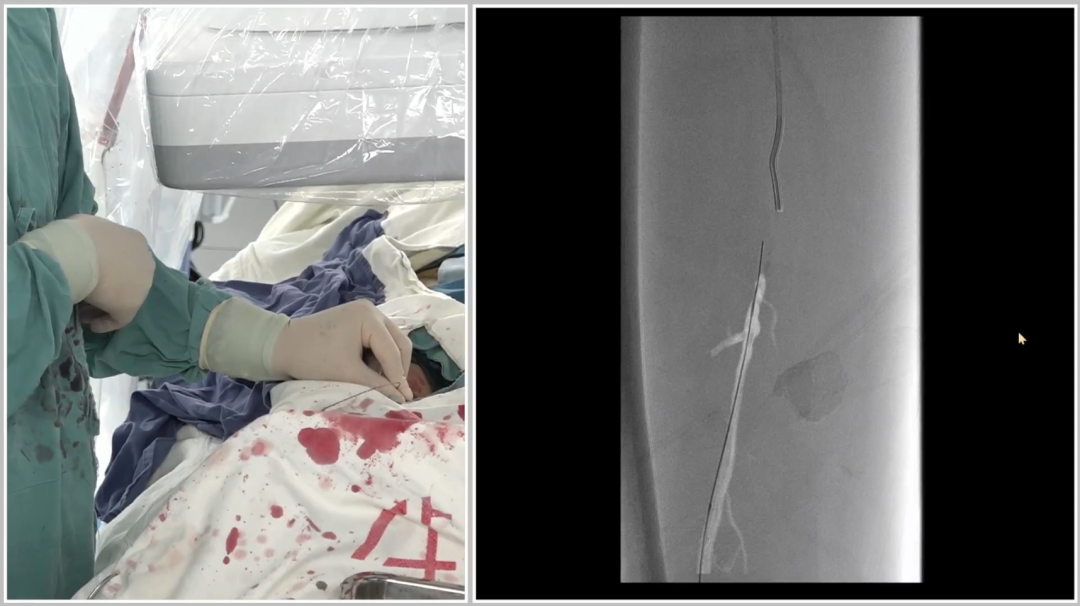

管腔准备与支架植入

预扩张:使用球囊扩张病变段,造影提示长段限流性夹层,需支架覆盖

治疗模式:因股腘动脉直径<4.5mm,选择DCB(药物涂层球囊)+BMS(裸金属支架)联合方案;

支架选择:在DCB扩张导管进行管腔准备后,植入2枚5mm INNOVA支架,其优势在于尾端定位精准,尤其适合累及开口或分叉的病变。